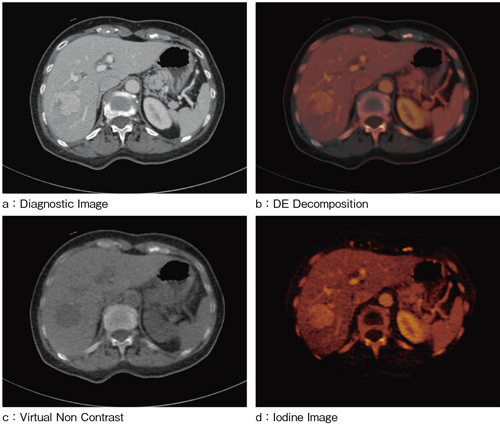

シーメンス社製のCT装置「SOMATOM Definition Flash」,あるいは「SOMATOM Definition」では,2つの異なる管電圧での撮影が可能である。高電圧と低電圧のデータをさまざまな形で解析することにより,造影剤や骨,軟部組織など,いままで分離が難しかった情報も分離,強調が可能である。最近では,腹部領域においてもDual Energy Imagingを用いた臨床応用が進んでいる。脂肪,軟部組織,造影剤の3つの組成を用いて解析を行う“Liver VNC”は,造影された画像から仮想的に,非造影画像の作成や,逆に造影剤を強調したIodine Imageを作成することができる(図2)。通常のCT画像だけでは肝臓等の腫瘍内の濃染状態が判断し難い場合にも,造影剤を強調するIodine Imageを用いることで,より詳しい病変情報を得ることができる。腫瘍濃染の情報が得られることは,がんの分化度判定へつながるであろう。

図2 CT Dual Energy